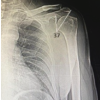

We had five patients who were diagnosed with SSS, out of which four were young male in the age group of 20–30 years, and one was a female who was 55 years old. Four of them had scapulothoracic bursitis and one had Lushka tubercle as the etiology. Two of them were swimmers, two were manual laborers, and one was a homemaker. On clinical examination, all the patients in the study demonstrated palpable and audible clicking sounds during scapulothoracic movements on the affected side (Fig. 1). None of them had any intra-articular pathology of the glenohumeral joint. Magnetic resonance imaging (MRI) revealed fibrous bands, thickened bursae, and ruled out any malignant conditions that may mimic scapulothoracic bursitis (Fig. 2). We performed MRI with contrast targeting the scapula, as routine shoulder MRI typically does not include the entire scapula with its medial border. T1- and T2-weighted fat-saturated sequences were performed in the coronal, sagittal, and axial planes of the scapula.

During the surgery, the patients were placed in a prone position with their arm in chicken winged position, two portals were made 3 cm medial to medial border of scapula, one just below the level of spine of scapula for arthroscope and one 5 cm below to that for the instrumentation (Fig 2). The bursoscopy revealed thick, inflamed bursae which were fibrotic with a lot of adherent fibrotic brands. Using a radiofrequency ablator and arthroscopic shaver, inflamed bursae were resected, and the scapula was freed from the thoracic wall regaining the full passive scapulothoracic motion (Fig. 3-6).